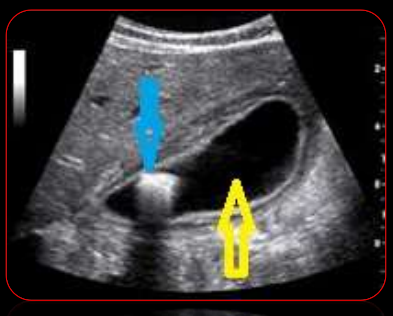

<p>Nomenclatura de la flehca azul y amarilla</p>

Nomenclatura de la flehca azul y amarilla

Hiperecogénico o Hiperecoico

Anecoico